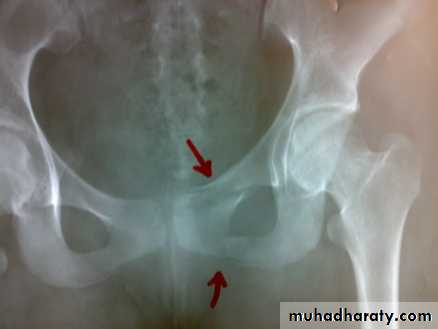

Fracture pubic ramai

Fracture pubic ramiFracture acetabulum